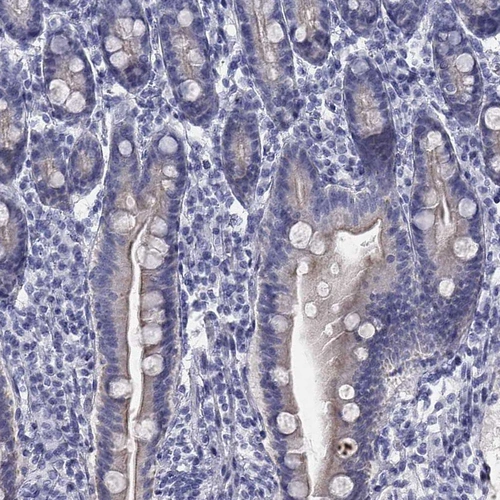

Immunohistochemistry analysis in human skin and lymph node tissues using HPA043539 antibody. Corresponding SULT2B1 RNA-seq data are presented for the same tissues.